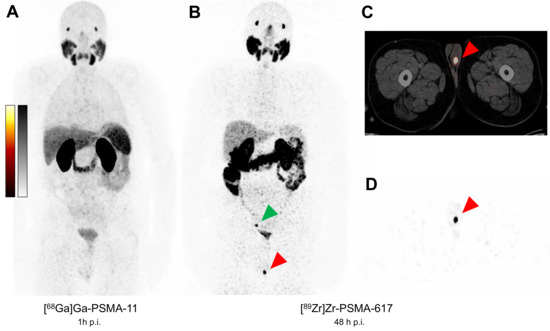

Histologically Confirmed Testicular Metastasis Revealed by [89Zr]Zr-PSMA-617 PET/CT in a Patient with Biochemical Recurrence of Prostate Cancer and Negative Conventional PSMA PET/CT Imaging